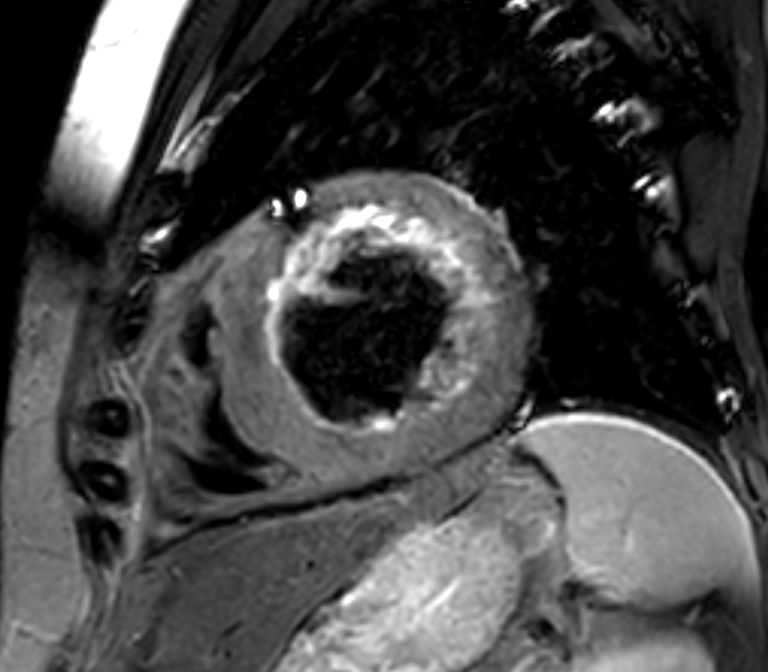

Short axis view T2w Black Blood

Short axis view 3D Late Gadolinium Enhancement